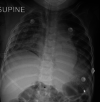

A bronchogenic cyst masquerading as asthma: A case report

Wheezing in infants and under-five children may present a diagnostic problem as there are various aetiologies for this symptom. Diagnosis of asthma is often made as it is one of the causes of wheezing in children. It is however important to have taken a complete history, including allergy and appropriate diagnostic investigations. If the child's symptoms do not improve despite appropriate therapy, a different diagnosis must be pursued. We report the case of a child who presented to us with wheezing and who did not respond to therapy.